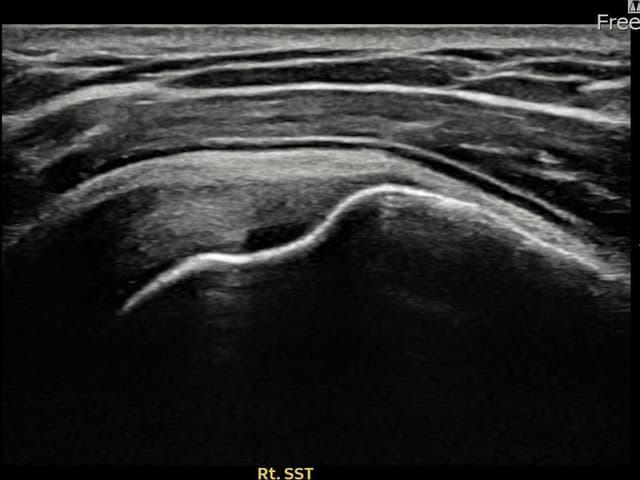

[経過期間: 23.08.16~23.10.18]

[縫縮術] 超音波検査にて右 棘上筋腱 関節面側部分断裂(7mm × 3mm (腱厚の約30%欠損))を確認。縫縮術施行後、腱の連続性が回復し、日常生活に復帰されました。